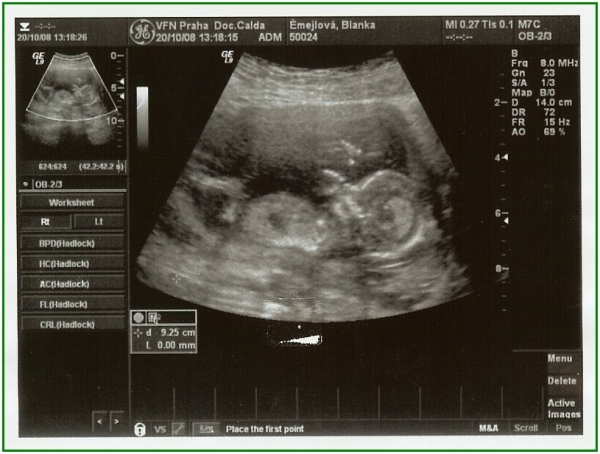

Pod pokličkou poprvé